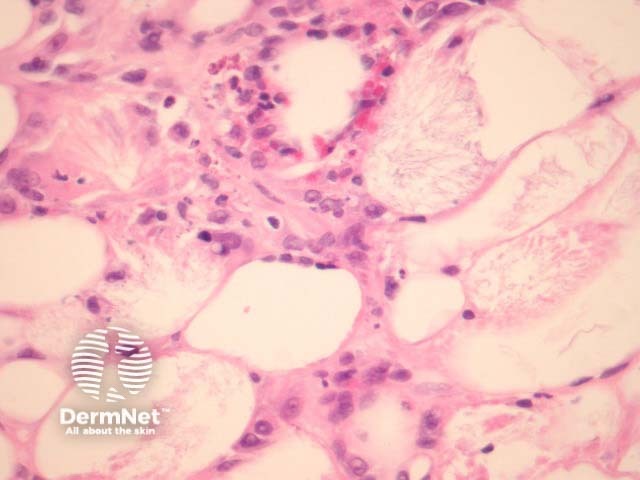

In subcutaneous fat necrosis of the newborn there is a lobular panniculitis with an infiltrate of mixed inflammatory cells. Needle-shaped clefts, in radial array, are seen in adipocytes and giant cells (figures 1–4) .